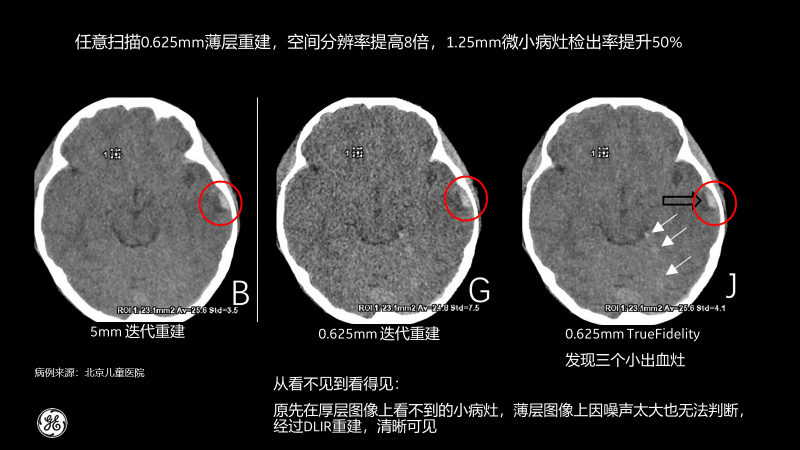

相比傳統(tǒng)CT圖像對腹部檢查一般都選擇5mm厚層重建,TrueFidelity可對任意體型任意部位的檢查進(jìn)行0.625mm的薄層圖像重建,真實(shí)還原圖像的解剖細(xì)節(jié)和紋理,提高微小病灶的發(fā)現(xiàn)幾率,有助于早診早治,極大提高醫(yī)生的診斷信心。

北京兒童醫(yī)院的測試病例也顯示,經(jīng)過TrueFidelity,任意掃描0.625mm薄層重建,空間分辨率能提高8倍,1.25mm微小病灶檢出率提升50%,最終額外發(fā)現(xiàn)了3個(gè)之前看不到的微小病灶。